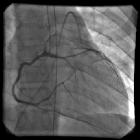

Similar to a prepulmonic or retroaortic course a transseptal course is apparently not of increased hemodynamic risk and might be found incidentally on invasive coronary angiography (ICA), cardiac CT or cardiac MRI. Other conceivable symptoms include angina or arrhythmia .

A transseptal or intraseptal course is usually associated with an ectopic origin of either left anterior descending artery, left main coronary artery or right coronary artery. It can be depicted on coronary CTA or coronary MRA or invasive coronary angiography (ICA) as a major coronary artery coursing through the interventricular septum .